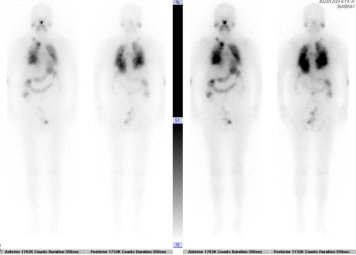

碘131全身显像(甲状腺癌术后,全身多处放射性浓聚,提示转移可能):